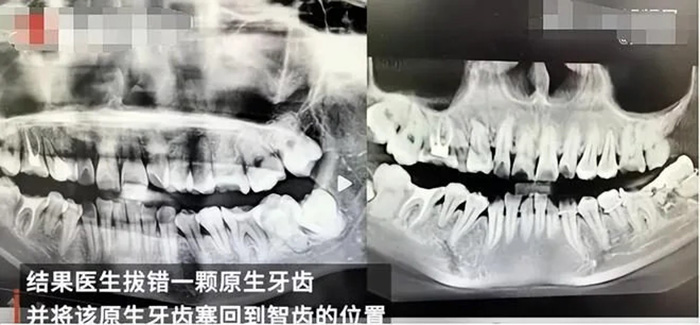

ในคลิปวิดีโอของหญิงสาวรายนี้ก่อนที่เธอจะเสียชีวิต แสดงให้เห็นว่า เธอร้องไห้เนื่องจากมีอาการเจ็บปวดทรมานมากจนนอนไม่หลับ นอกจากนี้ใบหน้าของเธอยังปวดบวม และเธอก็แทบจะกินอะไรไม่ได้ เพราะความเจ็บปวดอย่างรุนแรง โดยต่อมาเธอได้ไปที่โรงพยาบาลอีกแห่ง เพื่อเอกซเรย์ตรวจเช็กฟัน ทำให้ได้รู้ว่ามีการฉีดยาชาเข้าที่ฟันคุด แต่ฟันซี่ที่ถูกถอนออกมาผิดไม่ได้ฉีดยาชา